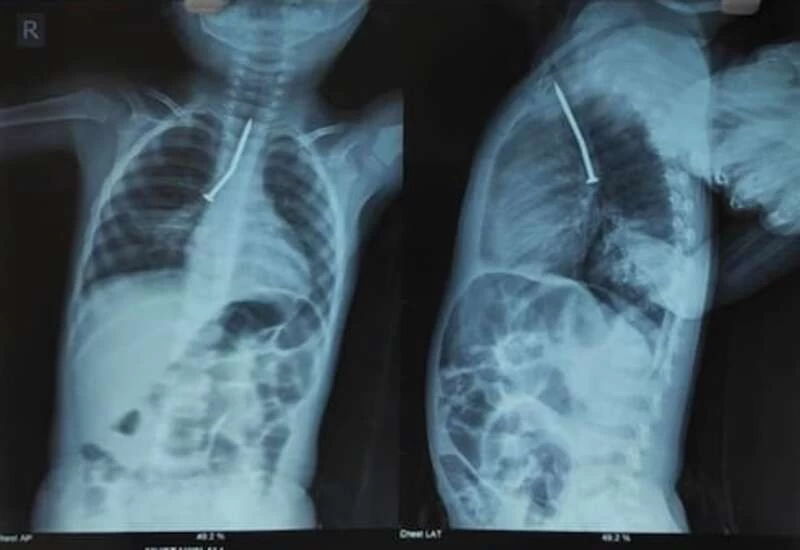

पश्चिम बंगाल (West Bengal) के उत्तरी दिनाजपुर के हटगाछी में रहने वाले बच्चे ने करीब ढाई इंच लंबी लोहे की कील (Iron Nail) को निगल लिया।कोलकाता। पश्चिम बंगाल (West Bengal) के उत्तरी दिनाजपुर के हटगाछी में रहने वाले बच्चे ने करीब ढाई इंच लंबी लोहे की कील (Iron Nail) को निगल लिया। इसके बाद जब उसकी तबीयत खराब होने लगी तो उसे अस्पताल ले जाया गया जहां डॉक्टरों ने ऑपरेशन करके उसकी जान बचाई। उत्तरी दिनाजपुर में रहने वाले दो साल के मुस्तकिन अली के दादा बांस काटकर उसे घर के बाहर लगा रहे थे। उनके पास में ही मुस्तकिन खेल रहा था। बीच में जब उनकी नजर उस पर पड़ी तो उन्होंने देखा कि वह खांस रहा है और उसके मुंह से खून बह रहा है।

इस मामले की जानकारी होने के बाद उसकी मां परेशान हो गई। इस पर उसकी मां उसे लेकर रायगंज मेडिकल कॉलेज पहुंची। उसे सांस लेने में दिक्कत हो रही थी और उलटी भी हो रही थी। वहां से मुस्तकिन को मालदा मेडिकल कॉलेज रेफर किया गया। इसके बाद उसे कोलकाता के एसएसकेएम में भर्ती कराया गया। वहां रविवार को डॉक्टरों ने कई घंटे उसका ऑपरेशन करके उसके गले से कील को बाहर निकाला। बच्चे को इसके बाद पेडियाट्रिक आईसीयू में रखा गया है।

एसएसकेएम मैनेजमेंट के अनुसार मुस्तकिन की सर्जरी रविवार को सुबह 7 बजे शुरू हुई थी। डॉ। अरुणव सेनगुप्ता के नेतृत्व में 4 डॉक्टरों की टीम ने उसका आपॅरेशन किया था। उनके अनुसार बच्चे की सांस की नली में कील फंस गई थी। इससे उसे उलटी हो रही थी और सांस लेने में दिक्कत थी।